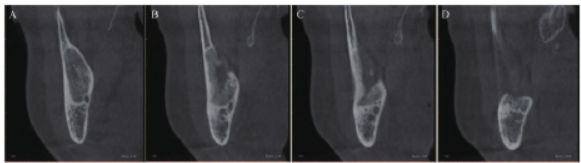

完善术前检查,患者于全身麻醉下行下颌骨病变切除术,术中切除右侧下颌骨内肿物。术后送肿物做组织病理学检查,苏木精-伊红(hematoxylineosin,HE)染色结果( 图3A、3B )显示:(右侧下颌骨肿物)符合IMC(高分化)。肿物由黏液细胞、中间型细胞及鳞状上皮细胞构成。免疫组织化学(immunohistochemistry,IHC)染色结果( 图3C—3G ):P40(+)、CK7(+)、CK56(+)、p63(+)、Ki67(+)、CK20(-)、S100(-)、GATA3(-)、GCDFP-15(-)、AR(+)、SOX-10(-)、Her-2(-)、CD117(-)、CEA(+)。为进一步明确诊断,采用荧光原位杂交(fluorescencein situ hybridization,FISH)技术对患者石蜡病理切片进行MAML2(11q21)基因断裂检测,检测结果( 图4 )为阳性。

术后8 个月复查,患者无疼痛、麻木等不适感,愈合良好,未见复发。影像学检查( 图5 、 图6 )提示,右侧下颌骨术区恢复愈合良好,可见明显骨修复。

图6 术后8 个月CBCT(矢状面)检查结果。A. 下颌骨内占位切除术后骨质修复;B. 骨质破坏后出现大部分骨修复;C. 颊侧骨皮质修复,下牙槽神经管结构恢复;D. 未见肿物再发。